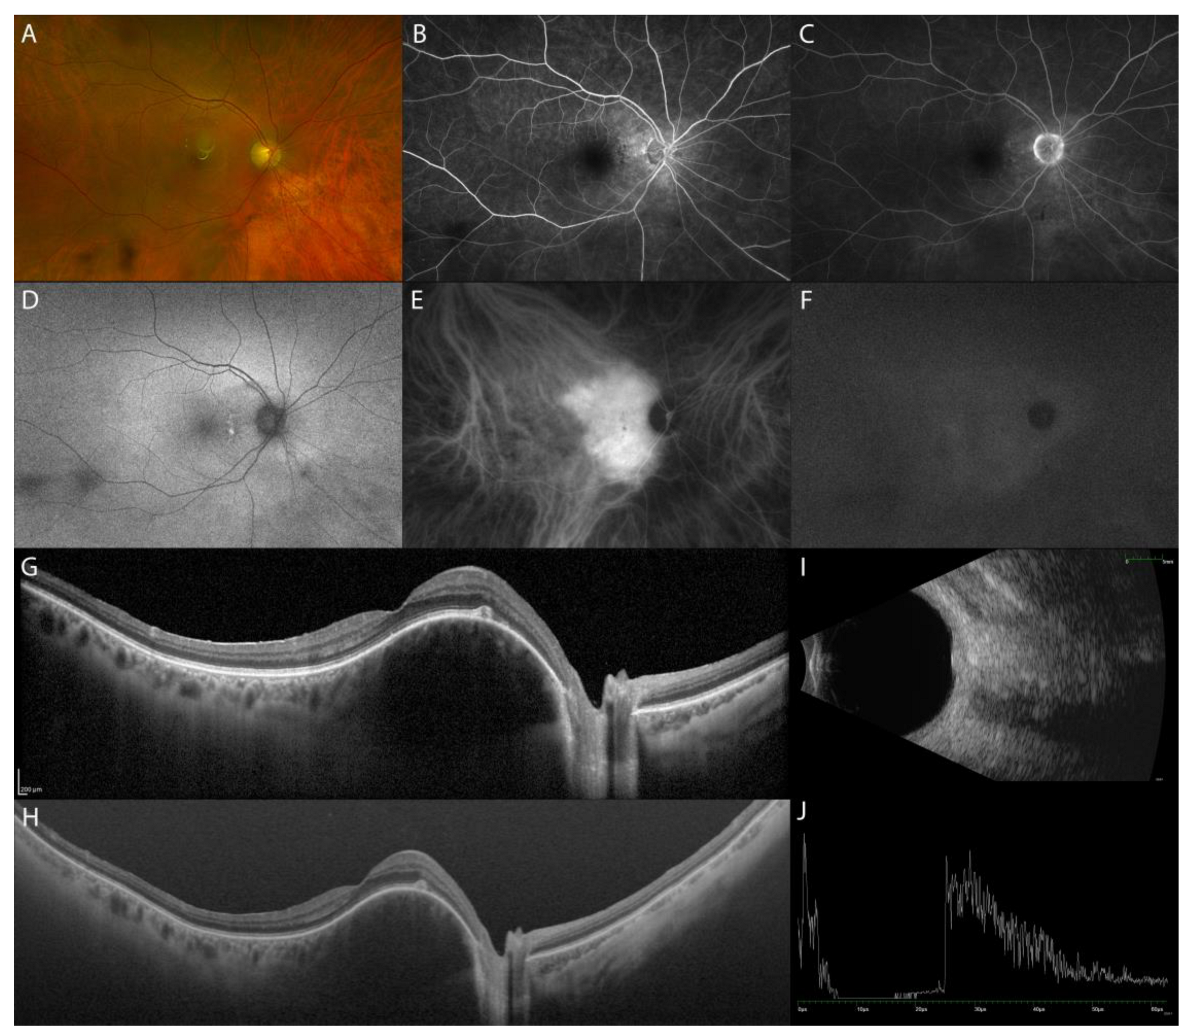

The acute uveitic phase of VKH disease is characterized by multifocal exudative retinal detachments (ERD) of the neurosensory retina secondary to diffuse granulomatous choroiditis (Figure 1A). In addition, the initial stage of the disease can present optic disc hyperemia and swelling, associated or alone [4].

Multimodal imaging (MMI) of the acute uveitic phase of VKH disease. Ultra-wide field (UWF) pseudocolor fundus image (Optos PLC, Dunfermline, Scotland, UK) with multifocal ERD (A). FA showing peripapillary and posterior pole hyperfluorescence, indicating pooling of the ERD and hyperfluorescence of the optic disc (B,E). Fundus autofluorescence imaging (FAF) highlighting the ERD (D). ICGA hyperfluorescence with leakage from the choroidal vessels and multiple hypofluorescent dots (C,F). EDI-OCT (Spectralis OCT, Heidelberg Engineering, Heidelberg, Germany) showing multifocal ERD (G), RPE undulation (H), and diffuse thickening of the choroid, which all reduce post-treatment (I,J).

Fluorescein angiography (FA) features indicate secondary retinal involvement as a consequence of severe choroiditis, including subretinal fluid pooling due to ERD and optic disc hyperfluorescence (Figure 1B,E). ICGA reveals signs of choroiditis characterized by the presence of hypofluorescent dark dots and vasculitis of choroidal vessels (fuzziness of the vessels) (Figure 1C,F) [5]. B-scan US of the eye displays ERD with associated diffuse low-to-medium reflective thickening of the choroid posteriorly [6].

In acute VKH disease associated uveitis, OCT shows ERD with subretinal fluid compartments separated by the typical septa (Figure 1G). Tsuboi et al. have described choroidal folds, which may be the result of a thickened choroid compressing Bruch’s membrane and RPE causing undulations of the RPE (Figure 1H). Choroidal folds were quantified using the RPE undulation index [7].

OCT can also be helpful in the early recognition of the predominantly optic disc swelling variant, which carries a worse prognosis [8]. In the acute phase of VKH disease, EDI-OCT reveals a markedly diffuse thickening of the choroid. Choroidal thickness may serve as a marker for the degree of choroidal inflammation, which gradually decreases with treatment (Figure 1I,J) [9]. SS-OCT provides better resolution images of the choroid than EDI-OCT does, resulting in more measurable images. When both SS-OCT and EDI-OCT images are readable, the measurements are comparable [10].